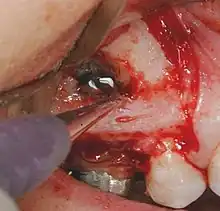

Chirurgie apicale: Principes généraux.

- On obtient une anesthésie convenable.

- On choisit un lambeau chirurgical approprié, et on envisage une réclinaison mucopériostée, traumatisante a minima.

- On pratique une ostéotomie en regard de la lésion, on suit la procédure appropriée et le lambeau est replacé et suturé.

- On prend une radio post opératoire.

- On conseille au patient les soins appropriés.